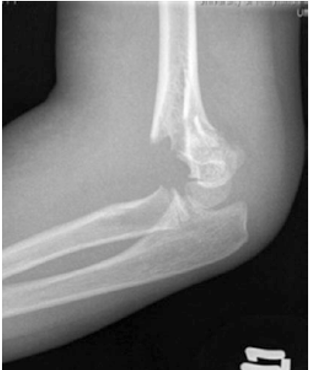

Hình 3:Gãy trên lồi cầu xương cánh tay Gartland độ IIB ,vỏxương phía sau còn nguyên vẹn kèm di lệch xoay ( Courtesy of Joshua M. Abzug, MD)